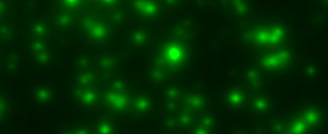

The data that result from the considered immunoassays are noisy images containing spots of different shapes and sizes, which may overlap and occlude each other (see Fig. 1 for an example section). From a biological perspective, the most relevant information in these images is the number of spots they contain and their precise location. The former is used to establish which proportion of the cells involved in an experiment secreted a substance of interest, while the latter is used to correlate this information with parallel assays for some other substance on the same cell population (multiplex assays). For example, in [10], a Fluorospot assay was run for the cytokines IFN-, IL-A and IL- to determine the proportion of human peripheral blood mononuclear cells that generated one, two or all of these substances under the effect of a specific antigen.

The spots in the considered images are the result of particles generated by cells (reaction) during a time window . These cells (hereon, active cells) are immobilized at the bottom of a well, i.e. on the plane . The particles they generate undergo a Brownian motion through a medium (diffusion), modeled here by the half-space . When these particles collide with the plane , they can bind to an even coat of receptors that covers it (adsorption), and after some time, they can break the bond and continue their motion (desorption). At time , the experiment finishes and the density of bound particles is imaged. Fig. 1 exemplifies this physical model at a particle level and exhibits a section of a real image from a Fluorospot immunoassay.

|

|

| (a) Particles’ motion model | (b) Typical observation |